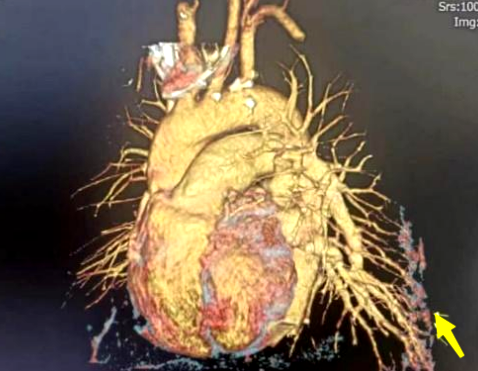

肺部血管CT造影提示肺内分流的血管